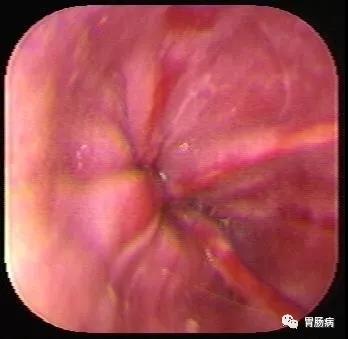

導 語反流性食管炎(RE)是由胃、十二指腸內容物反流入食管引起的食管炎癥性病變,內鏡下表現(xiàn)為食管黏膜的破損,即食管糜爛和(或)食管潰瘍,是我國高發(fā)疾病之一,今天簡述反流性食管炎的癥狀及中西醫(yī)治療。